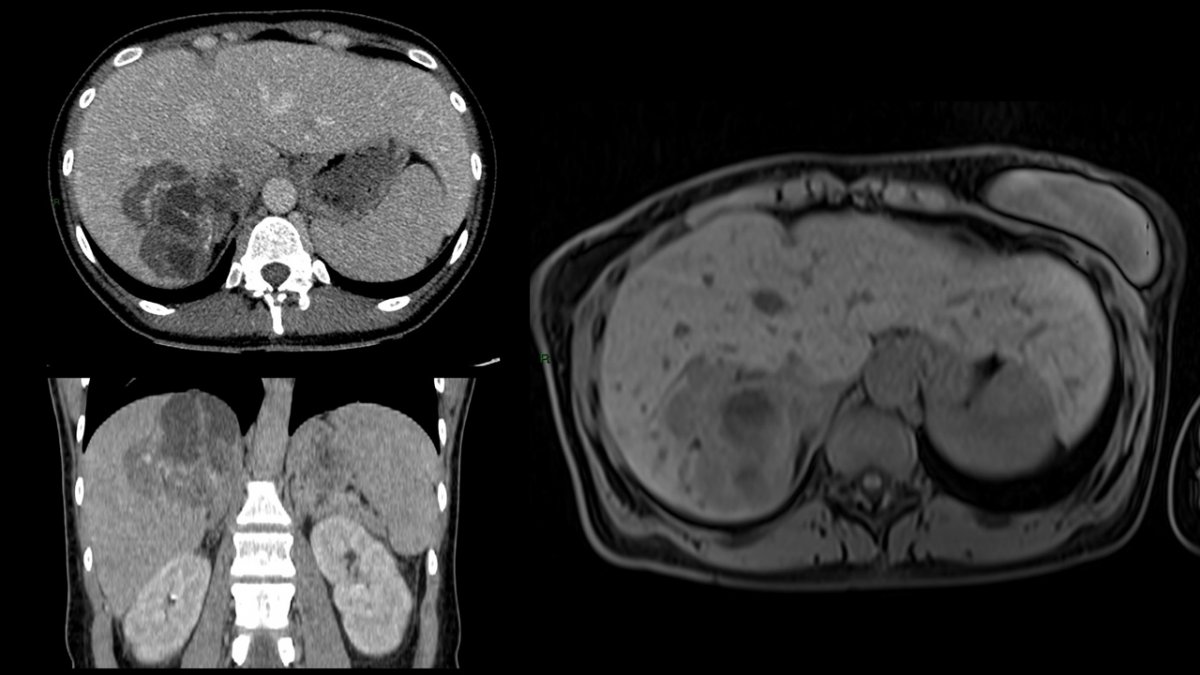

Zdroj: FNsP F. D. Roosevelta